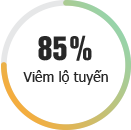

BỆNH PHỤ KHOA

Những bệnh lý ở “vùng kín” có thể đe dọa nghiêm trọng đến tâm lý, đời sống và đặc biệt là sức khỏe sinh sản của người phụ nữ. Đừng bao giờ chủ quan với các bệnh lý phụ khoa mà hãy khám và chữa bệnh kịp thời tại Phòng khám Đa khoa Quốc tế HN